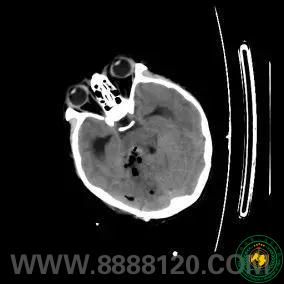

宜宾市第二人民医院扶贫记之神经外科篇

宜宾市第二人民医院 图文